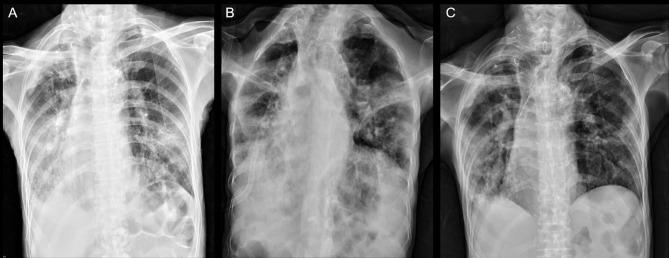

Herpes simplex virus type 1 (HSV1) pneumonia presents diagnostic challenges due to there being no gold-standard criteria currently. Specimens from bronchoalveolar lavage can increase specificity, and cytohistological examination can prove virus infection. Patients with high viral load have been reported with poor outcomes and benefited from antiviral agent. We describe an 80-year-old man with severe pneumonia who initially showed improvement without antiviral therapy, despite viral inclusion bodies on sputum cytology and positive HSV1 polymerase chain reaction from sputum, though subsequent clinical deterioration due to infection necessitated intensive care. This case highlights the complexities of diagnosing and managing HSV1 pneumonia, emphasizing the importance of integrating clinical suspicion, radiological imaging, and laboratory tests for timely therapeutic decisions in critically ill patients.

由于目前尚无金标准诊断标准,1型单纯疱疹病毒(HSV1)肺炎的诊断面临挑战。支气管肺泡灌洗标本可提高特异性,细胞组织学检查可证实病毒感染。据报道,病毒载量高的患者预后较差,抗病毒药物治疗有益。我们描述了一名80岁的重症肺炎男性患者,尽管痰细胞学检查发现病毒包涵体且痰HSV1聚合酶链反应呈阳性,但最初未接受抗病毒治疗时病情有所改善,不过随后因感染导致临床病情恶化,需要重症监护。该病例凸显了HSV1肺炎诊断和管理的复杂性,强调了在重症患者中综合临床怀疑、影像学检查和实验室检查以做出及时治疗决策的重要性。